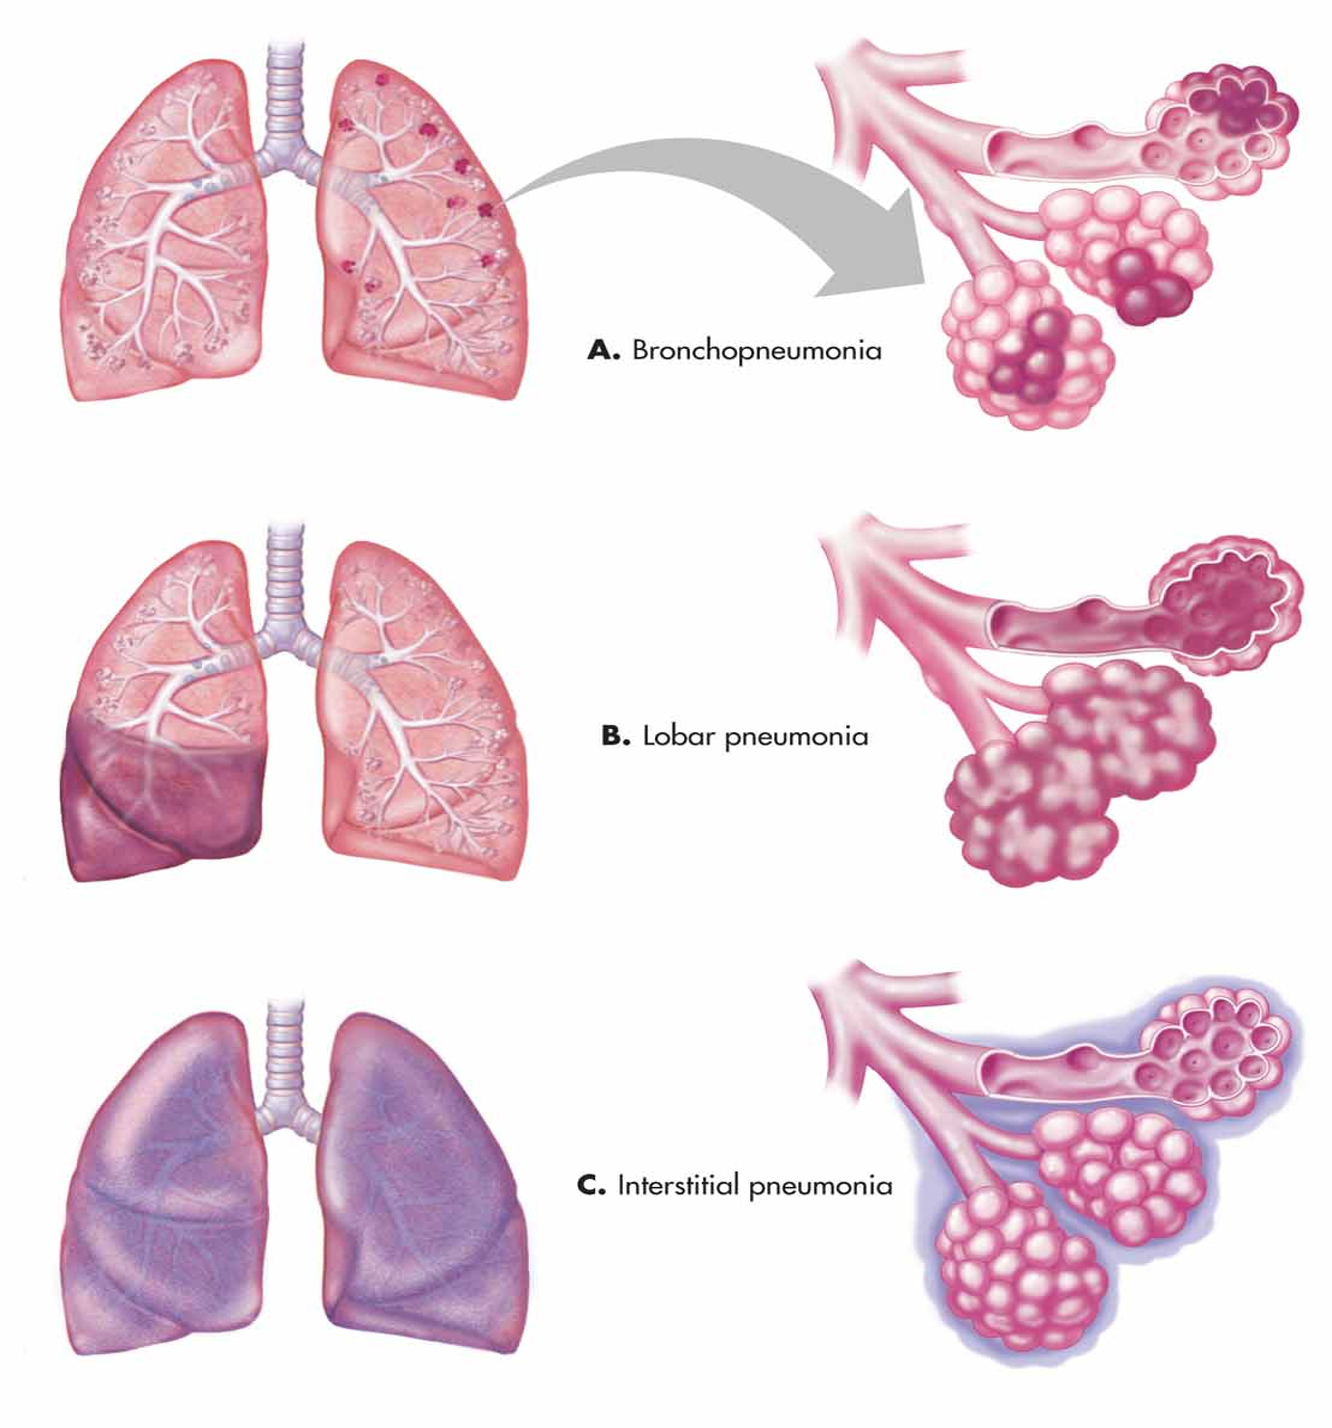

ANATOMICAL TYPES OF PNEUMONIA

-

Lobar pneumonia:

- Involvement of a single lobe or segment of a lobe; this is the classic pattern of S. pneumoniae pneumonia

-

Bronchopneumonia:

- Primary involvement of airways and surrounding interstitium; this pattern is sometimes seen in Streptococcus pyogenes and Staphylococcus aureus pneumonia

-

Necrotizing pneumonia:

- Associated with aspiration pneumonia and pneumonia resulting from S. pneumoniae, S. pyogenes, and S. aureus)

-

Caseating granuloma (as in tuberculosis pneumonia)

-

Interstitial and peribronchiolar with secondary parenchymal infiltration:

- This pattern typically occurs when a severe viral pneumonia is complicated by bacterial pneumonia